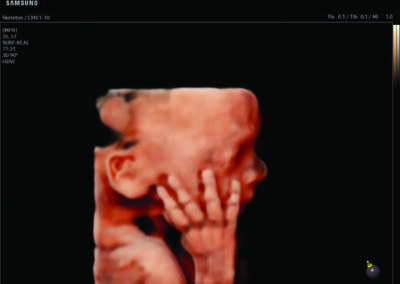

Comprehensive, advanced and expert MFM care for high-risk pregnancies